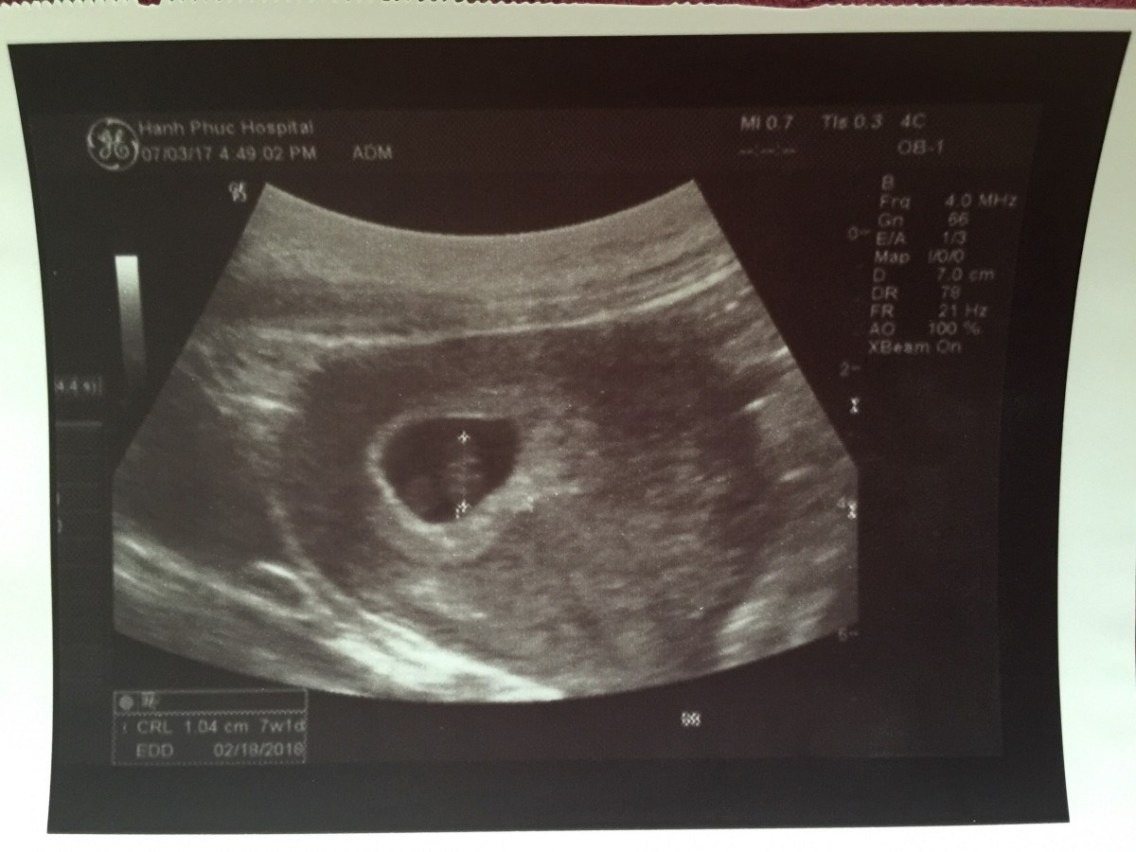

Kích thước thai nhi 7 tuần đạt tương đương quả việt quất, nặng khoảng 1g và dài từ 6 - 10mm.

Nhịp tim thai 7 tuần trung bình từ 90 – 110 nhịp/phút và có sự tăng nhẹ mỗi ngày. Các tế bào của hệ thần kinh liên kết với nhau tạo thành một chỉnh thể hoàn thiện, giúp điều khiển và quản lý hoạt động của các cơ quan khác trong cơ thể. Hệ thống tiêu hóa và bài tiết cũng đang trong quá trình cải thiện về mặt chức năng.

Thai nhi 7 tuần tuổi đã có những bước phát triển nhất định cả về hình dáng bên ngoài cũng như các chức năng bên trong của cơ thể. Chính vì thế, đây là giai đoạn thích hợp để mẹ bầu tiến hành siêu âm hình ảnh thai nhi và kiểm tra quá trình phát triển của bé yêu. Hình ảnh siêu âm thai 7 tuần tuổi sẽ cho biết nhiều chỉ số sức khỏe quan trọng giúp mẹ hình dung rõ ràng, cụ thể mức độ phát triển của bé yêu vào thời điểm này.